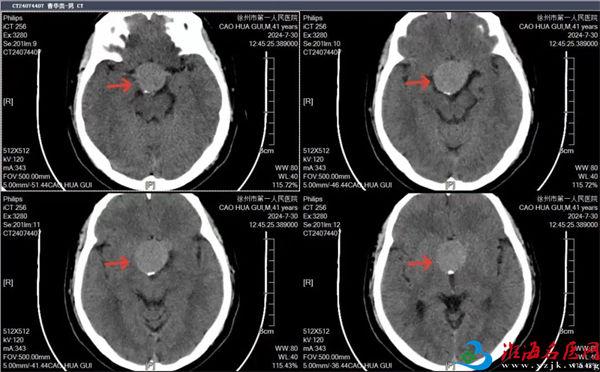

戈振华初步判断:患者的“病根儿”应该在颅内,行头颅CT,显示鞍区占位。

徐州一院神经外科神经功能亚专业组组长、副主任医师汤计磊会诊后,结合专科体检和患者头颅CT报告,考虑垂体瘤可能,已出现视神经压迫症状,建议住院进一步检查和治疗。

“入院行磁共振检查,诊断为:侵袭性垂体腺瘤,Knosp 4级。鞍区见4.5cmx3.2cmx3.6cm团块影,形态欠规则,局部分叶状;病灶向上突入鞍上池,挤压并突入三脑室;大脑前动脉、前交通动脉挤压移位;垂体柄及视交叉显示不清,病灶部分包绕两侧颈内动脉。”

“垂体相关激素检查虽无明显异常,但瘤体挤压视交叉压迫严重,视力减退,视野缺损、双颞侧偏盲,有明确的手术指征。”汤计磊把手术的必要性详细告知患者。